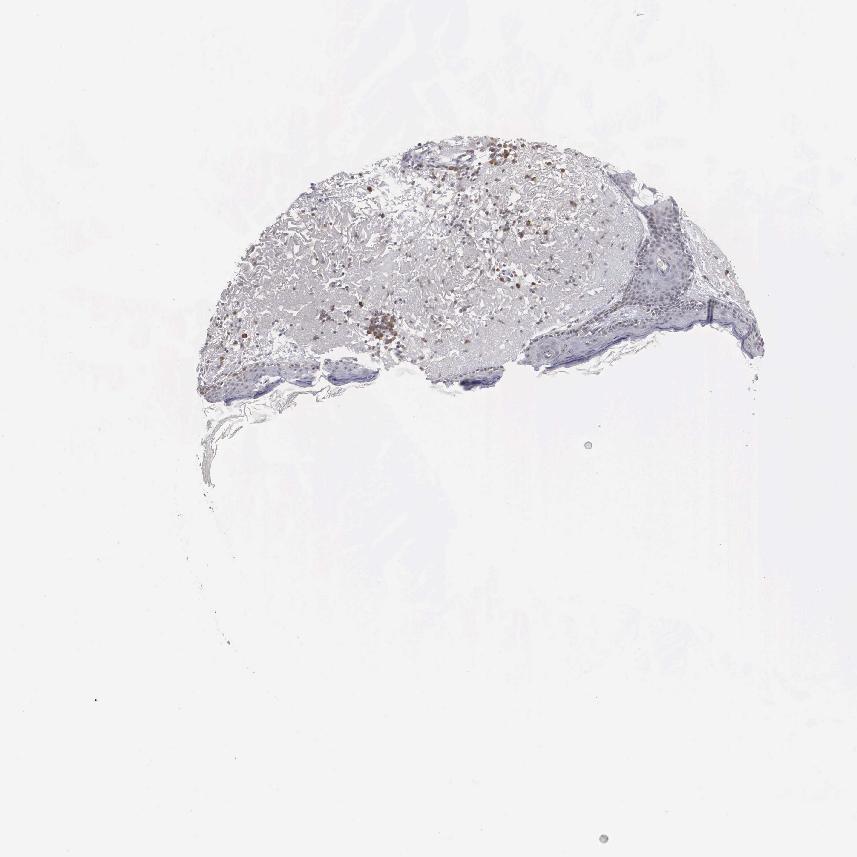

SKIN 1 - Antibody stainingi

Antibody staining in the annotated cell types in the current human tissue is reported as not detected, low, medium, or high, based on conventional immunohistochemistry profiling in selected tissues. This score is based on the combination of the staining intensity and fraction of stained cells.

Each image is clickable and will lead to virtual microscopy that enables deeper exploration of all samples and also displays staining intensity scores, fraction scores and subcellular localization as well as patient and tissue information for each sample.

Antibody HPA000813

Langerhans Not detected

Fibroblasts Not detected

Keratinocytes Not detected

Melanocytes Not detected

SKIN 2 - Antibody stainingi

Epidermal cells Not detected